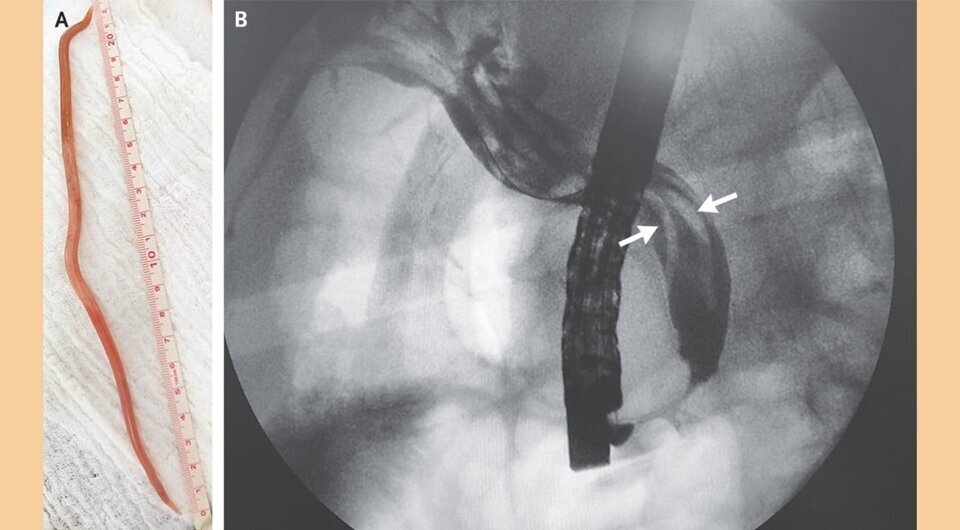

В желчном пузыре колумбийца нашли три 20-сантиметровых круглых червя

75-летний колумбиец поступил в отделение неотложной помощи с жалобами на лихорадку, обесцвеченный стул и боли в животе, которые беспокоили его в течение трех недель. При осмотре врачи отметили повышение температура тела, желтуху и болезненность в правом подреберье. Лабораторные исследования показали воспалительные изменения в организме и повышенное содержание конъюгированного билирубина. Ультразвуковое исследование правого подреберья показало застой желчи в общем желчном протоке и трубчатые структуры внутри него. Пациенту провели эндоскопическую операцию (ретроградную холангиопанкреатографию), во время которой врачи обнаружили червя, выступающего из фатерова сосочка. Это был круглый червь Ascaris lumbricoides — возбудитель аскаридоза. В дальнейшем врачи нашли в этом месте еще двух червей. Случай описан в The New England Journal of Medicine.

При аскаридозе из яиц червей в кишечнике выходят личинки, которые через венозные сосуды с током крови попадают в печень, а затем — в легкие. Вместе с бронхиальным секретом, выходящим из легких, личинки проглатываются и вновь возвращаются в тонкую кишку, где из них развиваются половозрелые особи. Пациент проживает на юго-западе Колумбии, где наблюдаются проблемы с доступом к чистой воде. Каждый червь был длиной более 20 сантиметров, их удаляли с помощью баллонного катетера. Дополнительно пациенту назначили альбендазол, и через неделю он стал чувствовать себя лучше.